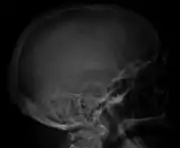

The diagnostic examination of a person with suspected multiple myeloma typically includes a skeletal survey. This is a series of X-rays of the skull, axial skeleton, and proximal long bones. Myeloma activity sometimes appears as "lytic lesions" (with local disappearance of normal bone due to resorption) or as "punched-out lesions" on the skull X-ray ("raindrop skull"). Lesions may also be sclerotic, which is seen as radiodense.[70] Overall, the radiodensity of myeloma is between −30 and 120 Hounsfield units (HU).[71] Magnetic resonance imaging is more sensitive than simple X-rays in the detection of lytic lesions, and may supersede a skeletal survey, especially when vertebral disease is suspected. Occasionally, a CT scan is performed to measure the size of soft-tissue plasmacytomas. Nuclear Medicine Bone scans are typically not of any additional value in the workup of people with myeloma (no new bone formation; lytic lesions not well visualized on nuclear bone scan).

- Skull X-ray showing multiple lucencies due to multiple myeloma